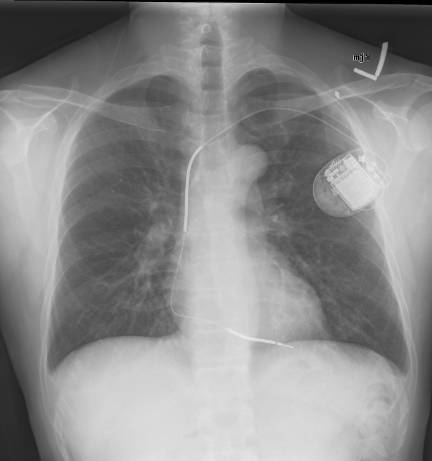

An automated implantable cardioverter defibrillator (AICD)

"The ICD is the first-line treatment and prophylactic therapy for patients at risk for sudden cardiac death due to ventricular fibrillation and ventricular tachycardia."

So no going through metal detectors at an airport. Let's see if this one comes with an app.